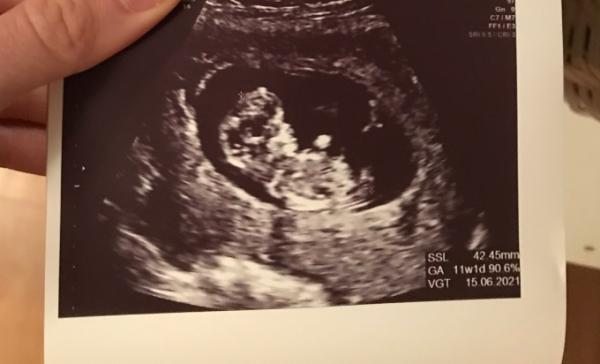

Hallo Liebe Leute, ich bin so glücklich und muss meine Freude mit euch teilen. Wir hatten heute den ersten großen US mit Nackenfaltmessung , bin heute 10+3 laut Ausmessungen des Zwerges 11+1 der Doc wollte es aber nicht mehr ändern weil er der Meinung ist die Zwerge kommen sowieso wann sie wollen und es ist nur ein richt Wert ( der Meinung bin ich übrigens auch) es war alles super die Messung war unauffällig und das gröbste Risiko hätten wir somit ja eigentlich auch überstanden Der Krümmel war so aktiv und ich wieder einmal so begeistert obwohl es meine 4 ss ist Ich bin so verliebt und die Geschwister freuen sich auch meger

Bild zu US und Nackenfaltmessung - Forum für Juni - Mamis